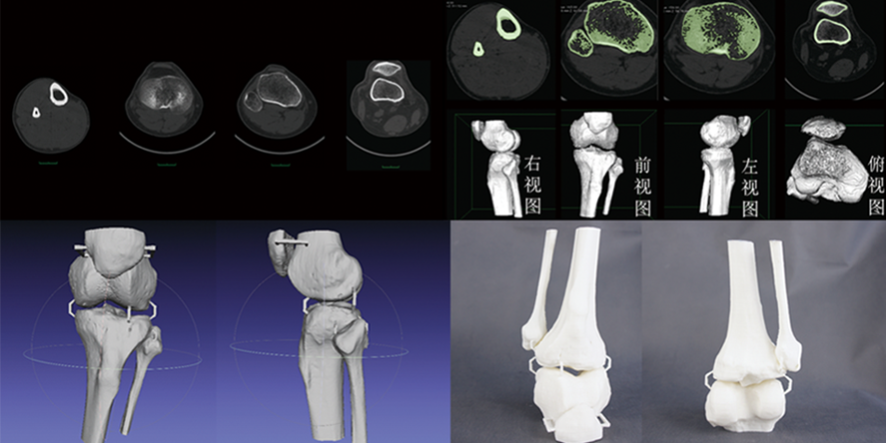

提高骨科手术效果:3D打印骨骼和CT数据三维建模技术在骨科手术中的应用